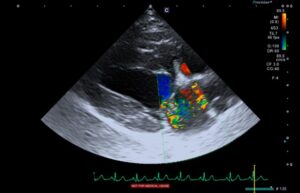

↑ 上の写真は、犬の心臓エコー検査写真です。

■ カラフルなモザイク模様の部分がありますが、ここは僧帽弁から左心房に逆流した血流です。

■ この血流が多いと、左心房が膨らんで容積が大きくなってきます。